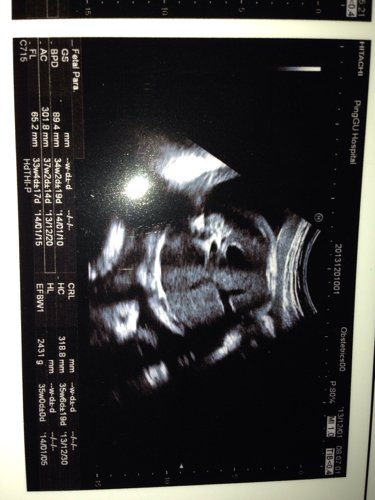

我怀孕34+2,今天检查医生说孩子头大,腿短,我还缺铁性贫血,我怕早产,我24周岁!想咨询孩子怎么 我怀孕34+2,今天检查医生说孩子头大,腿短,我还缺铁性贫血,我怕早产,我24周岁!想咨询孩子怎么样,多少斤了,会不会早产 点击展开 匿名用户 2013-12-02 00:10 为您推荐: 其他回答 病情分析: 你好,以双顶颈来判断胎儿的发育大小,只是一个参考性的数据。 指导意见: 在30周以后,允许有上下两周的误差,建议及时复查. 独水凡_xjeq 2013-12-02 09:53 相关问题 我怀孕34周两天,检查缺铁性贫血,怕孩子早产,不知道正常不正常,还说孩子头大,腿短 孕妇缺铁性贫血吃铁之缘片可以吗 是一位医生说的 可是上面写着保健食品不可代替药物 怀孕33周 股骨长径58mm 医生说会比正常人腿短点 这个严重吗?